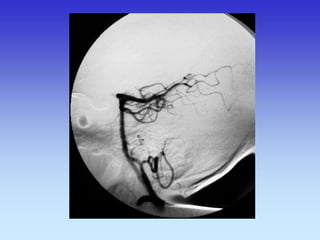

METODE PRIKAZA KRVNIH ŽILA

•UZ-DOPPLER

•DSA

•CTA

•MRA

A-V MALFORMACIJA